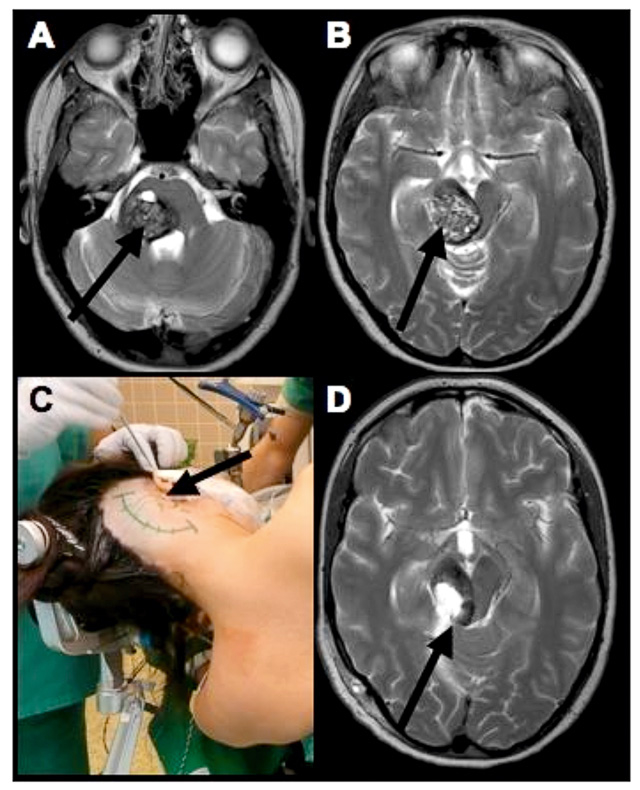

Figure 1

A 25 yo/f suffering from a right pontomesencephalic cavernomal haemorrhage (arrows) with subacute ataxia, hemiparesis and facial palsy (A and B). The surgery was performed on the left side via a combined supracerebellar and retrosigmoid approach (C). The arrows represent the approach to the cavernoma. Postoperative MRI image in T2 (D) revealed complete resection of the cavernoma with residual haemosiderin from the haemorrhages in the intact brainstem tissue (arrow). Postoperatively, only a temporary slight increase of ataxia was noted and further follow-up showed almost complete resolution of the preoperative symptoms.

A great variety of surgical approaches, such as the suboccipital midline, retrosigmoid or subtemporal approaches exist in many instances of brainstem cavernoma [5, 8, 10, 16, 17, 22, 23, 30]. The choice of the proper approach depends on the relationship between the cavernoma and the pial or ependymal surface of the brainstem. As the floor of the fourth ventricle contains structures with important functions [3, 23], a lateral entry is preferred whenever possible. The supracerebellar infratentorial approach (fig. 1) is suitable for many lesions and has yielded favourable patient outcomes; it is one of our preferred access routes. Intraoperative electrophysiological monitoring of long tracks (MEP and SEP), AEP and cranial nerves is obligatory during brainstem surgery [2, 25].